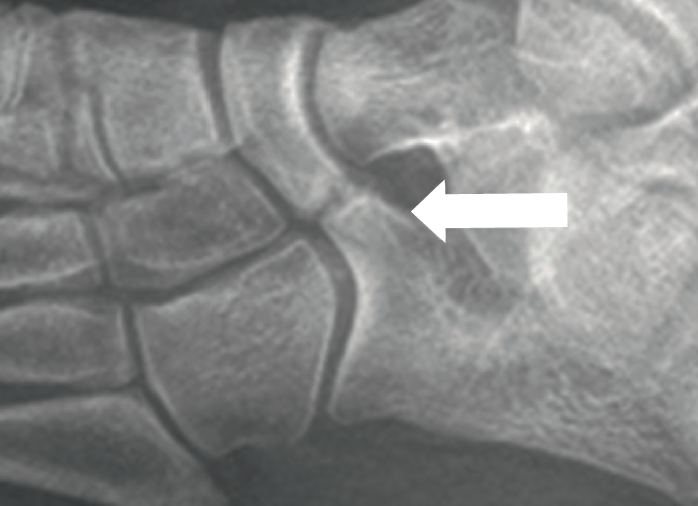

- Coaliciones calcaneoescafoideas. En el 90-100% de ellas es visible el denominado signo en “hocico o trompa de oso hormiguero” (Figura 1), apreciándose una prolongación del calcáneo hacia el escafoides, en la proyección oblicua. La existencia de un pico óseo dorsal en la cabeza de astrágalo no es tan frecuente de encontrar en estas coaliciones como en las talocalcáneas.

Figura 1. Imagen radiográfica oblicua donde se aprecia el signo en “hocico o trompa de oso hormiguero” en una coalición calcaneoescafoidea.